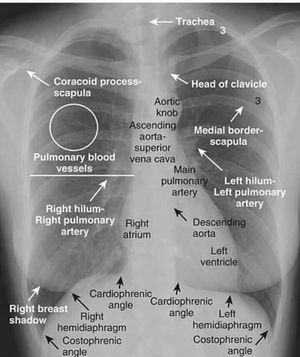

Normal chest x-ray

Medicine

Radiology